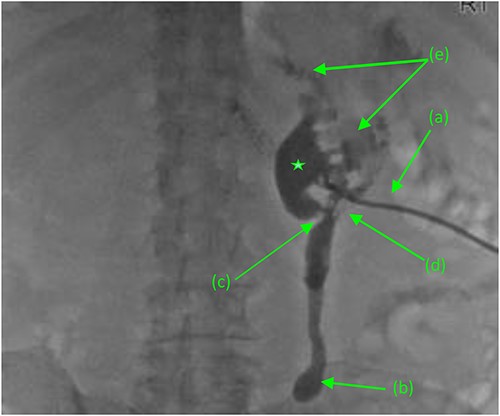

Antegrade pyelogram (prone position) revealing (a) right percutaneous nephrostomy tube (PCN), following the failed ureteral stent placement due to a distal ureteral stricture with subsequent (b) right sided hydroureter and abrupt cutoff. (*) Right sided hydronephrosis, secondary to (c) a second, more proximal ureteral stricture with a (d) frank fistulous connection tracking between the proximal ureter and duodenum. (e) Suspected retrograde leakage of contrast media from the right renal pelvis into the duodenum.